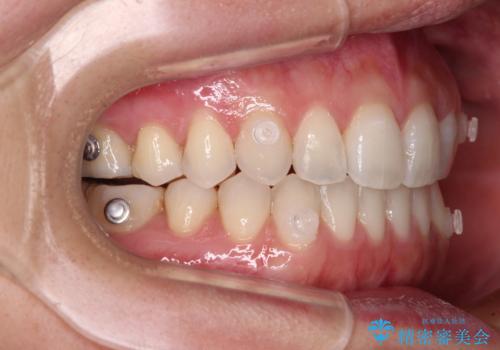

【モニター】狭い上顎歯列とオープンバイト 急速拡大装置を用いた矯正治療

- インビザライン

- 前歯の開咬を気にして来院された患者様です。

上顎歯列が狭窄していたため、急速拡大装置により上顎骨を側方に拡大し、その後インビザラインにて矯正治療を行うこととしました。